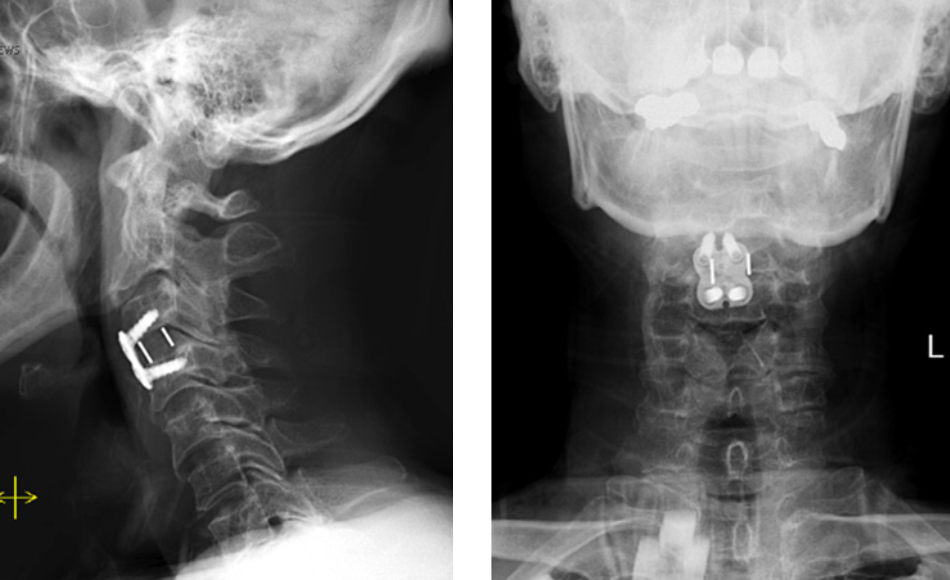

Figure 2. Lateral and AP cervical spine x-rays s/p ACDF

Dr. Imani performed an Anterior Cervical Discectomy and Fusion to remove the pressure of the herniated disc from compressing the spinal cord and stabilizing the spinal column with a fusion of the C3/C4 disc space.

After Dr. Imani’s surgery, the patient is making a full recovery. He is able to walk and move both arms/hands.